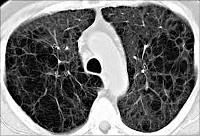

Диагностика буллезной эмфиземы легких основывается на клинических, функциональных и рентгенологических данных. Курация больного осуществляется пульмонологом, а при развитии осложнений - торакальным хирургом. Рентгенография легких не всегда эффективна в выявлении буллезной эмфиземы легких. В то же время, возможности лучевой диагностики существенно расширяет внедрение в практику КТ высокого разрешения. На томограммах буллы определяются как тонкостенные полости с четкими и ровными контурами. При сомнительном диагнозе удостовериться в наличии булл позволяет диагностическая торакоскопия.